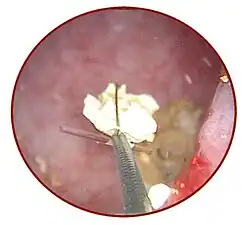

Die häufigste Ursache für Verlegungen des Harnleiters sind Harnleitersteine.[74] Da die Passage des Urins durch den Harnleiter relativ rasch verläuft, entstehen Harnleitersteine meist im Bereich der Niere als Nierenstein und verkeilen sich dann bei der Passage im Harnleiter. Harnleitersteine können nach Art ihrer Entstehung verschiedene chemische Zusammensetzungen haben.[75] In den Industrieländern beträgt die Inzidenz von Harnsteinen etwa 10 %, mit steigender Tendenz.[74] Auch bei Hunden und Katzen sind Harnsteine die häufigste Ursache für Harnleiterobstruktionen,[76] aber prinzipiell können alle Tierarten betroffen sein. Es gibt Fallberichte zu Pferden,[77] Kaninchen,[78] Meerschweinchen,[79] Zwergottern,[80] Delfinen[81] und Vögeln[82]. Durch krampfartige Muskelaktionen versucht der Harnleiter, die Steine weiter zu transportieren, was als schmerzhafte Harnleiter-Kolik wahrgenommen wird. Die wehenartigen heftigen Schmerzen strahlen je nach Lokalisation des Steins in den Rücken, den Bauch, die Leiste oder die Genitalien aus. Häufig kommt es auch zu Blutbeimengungen im Urin (Mikrohämaturie oder Makrohämaturie).[74] Bei erschwertem Abfluss hypertrophiert die Uretermuskulatur oberhalb des Hindernisses rasch. Die Steine werden heute vor allem ureteroskopisch bzw. antegrad ureteroskopisch mittels Laser-Lithotripsie oder von außen mittels extrakorporaler Stoßwellenlithotripsie zertrümmert.[83] Führt dies nicht zum Erfolg, muss der Stein durch Eröffnung des Harnleiters (Ureterolithotomie) entfernt werden, die heute vor allem laparoskopisch erfolgt.[84] Hier besteht anschließend immer die Gefahr der Entstehung von narbigen Einengungen (Strikturen), weshalb meist auch eine Harnleiterschienung durchgeführt wird.[85] Harnleiterschienen werden auch bei Harnleiterstrikturen anderer Ursache oder bei Nierensteinen eingesetzt.[86]